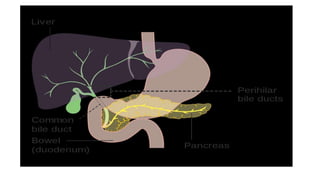

Head of pancreas

• The head of the pancreas is nestled in the C-loop of the duodenum

and is posterior to the transverse mesocolon.

• Just posterior to the head of the pancreas lie the vena cava, the right

renal artery and both renal veins

• The common bile duct runs in a deep groove on the posterior aspect

of the pancreatic head

Pancreatic Duct Anatomy

• The duct of the ventral anlage becomes the duct of Wirsung, and the

duct from the dorsal anlage becomes the duct of Santorini.

• The ducts from each anlage usually fuse together in the pancreatic

head

• most of the pancreas drains through the duct of Wirsung, or main

pancreatic duct, into the common channel formed from the bile duct

and pancreatic duct.

• The length of the common channel is variable.